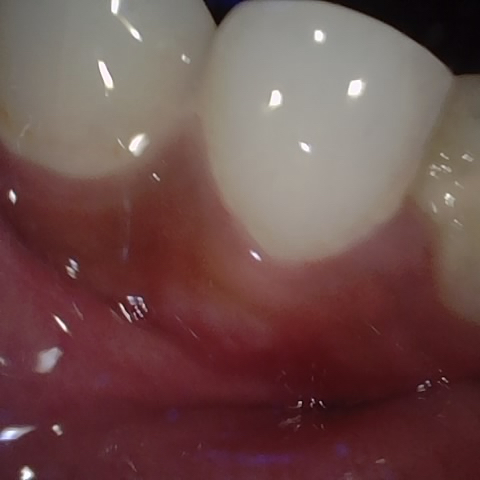

Annotated as "Bad"